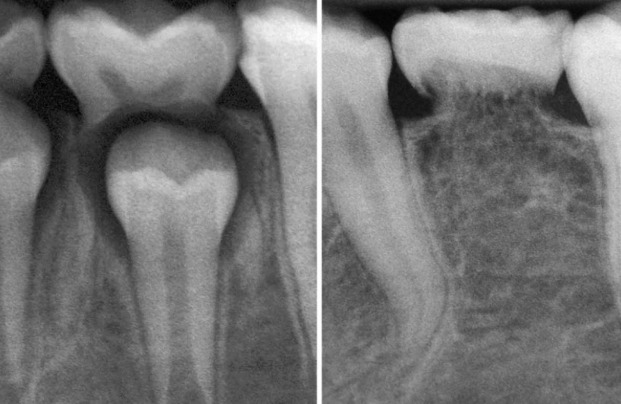

Os dentes decíduos são menores que os permanentes, tem formas, cor e tamanhos diferentes, com carga mastigatória menor a absorver. As forças oclusais de um adulto são lesivas para os tecidos periodontais do decíduo, gerando um trauma oclusal se houver reanatomização, acelerando a rizólise.

Quando um decíduo, ou “aquele que cai”, permanece no adulto, ele tende a ficar em infraoclusão, um nível de mordida mais baixo que os demais. Os vizinhos se inclinam vagorosamente em sua direção, pois são menores. A linha média se desvia, a oclusão se altera e atrapalha a mastigação e fonética.

A rizólise é um processo lento, demora meses e até anos. Quando se tem um dente permanente por baixo, entre as raízes dos dentes decíduos, o processo se acelera, pois em volta da coroa do dente permanente, tem uma membrana chamada folículo pericoronário que tem muito epitélio e libera o mediador chamado EGF que acelera a atividade dos osteoclastos e o processo da reabsorção decídua (Fator de Crescimento Epitelial). A rizólise se acelera muito e o decíduo fica sem a raiz e se exfolia.

Sem as células na raiz pela “Apoptose”, o osso encosta no dente e integra-os em sua estrutura e vai substituindo-o, até ficar completamente sem raiz. Depois de um ano sem a rizólise acelerada pelos permanentes, a tendência é do dente decíduo entrar em anquilose e reabsorção por substituição, pois os restos epiteliais também morrem por “Apoptose”. Isto também faz parte da rizólise e se chama anquilose e reabsorção dentária por substituição.